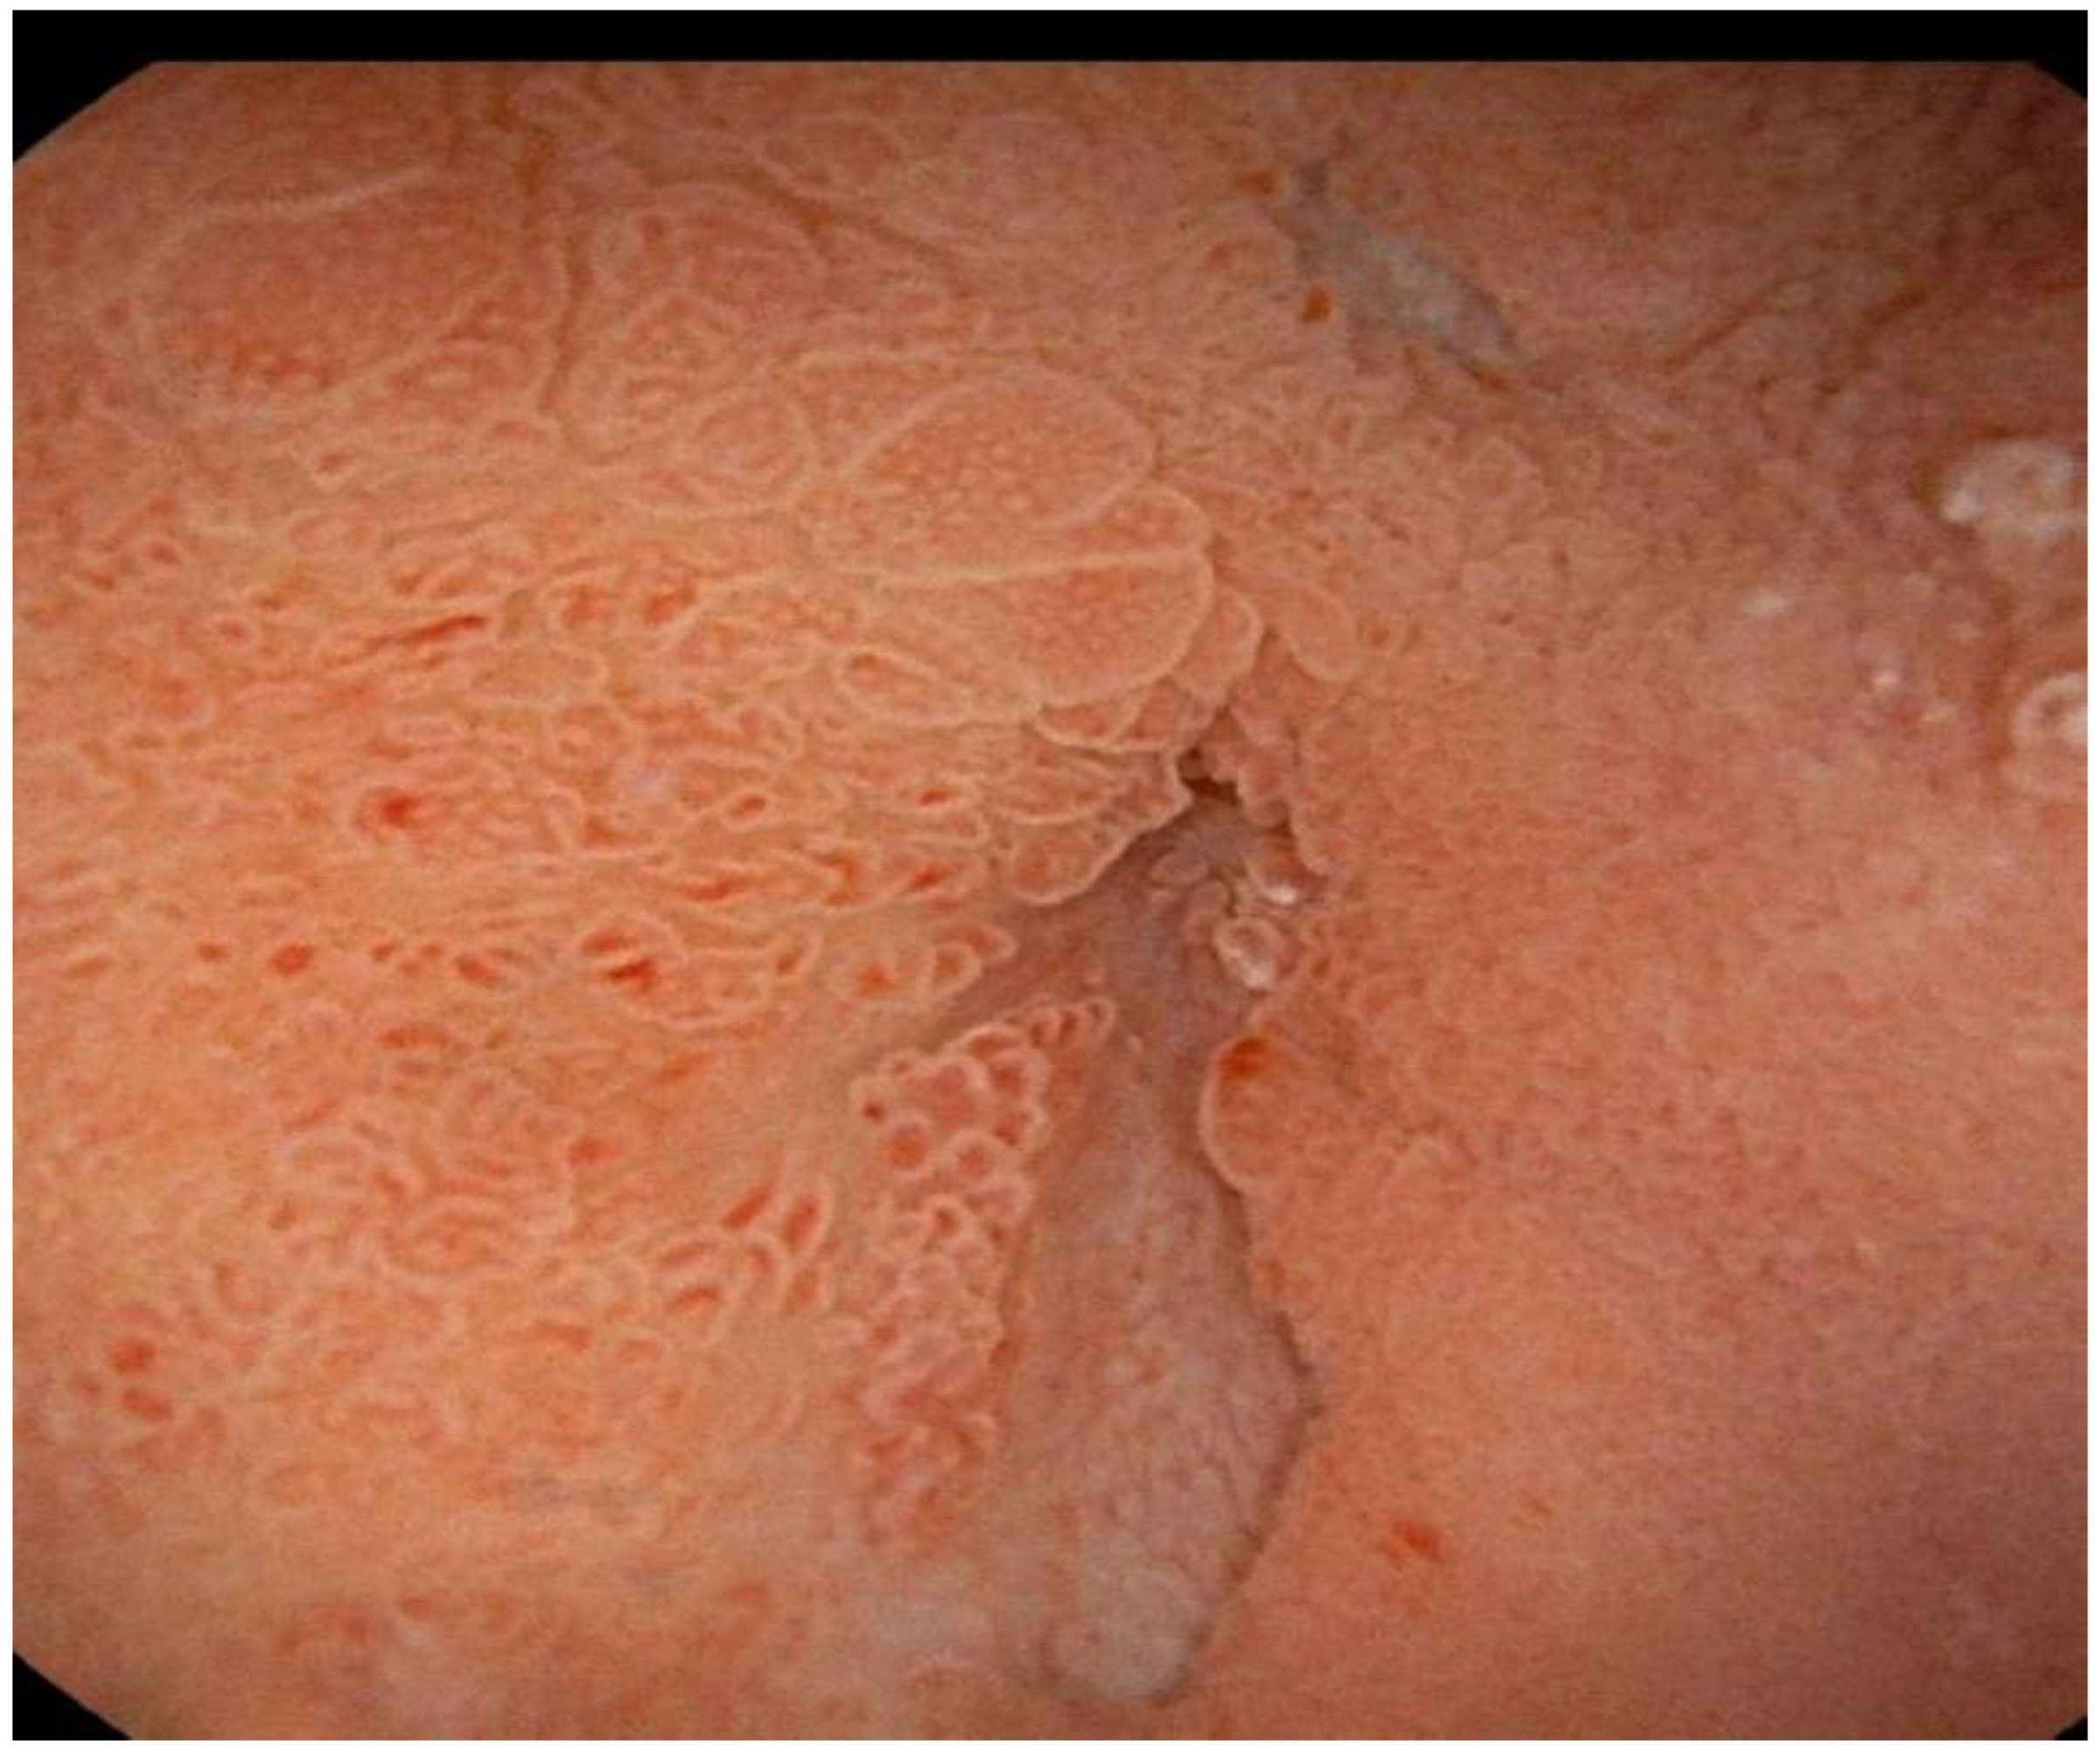

2. Case Report